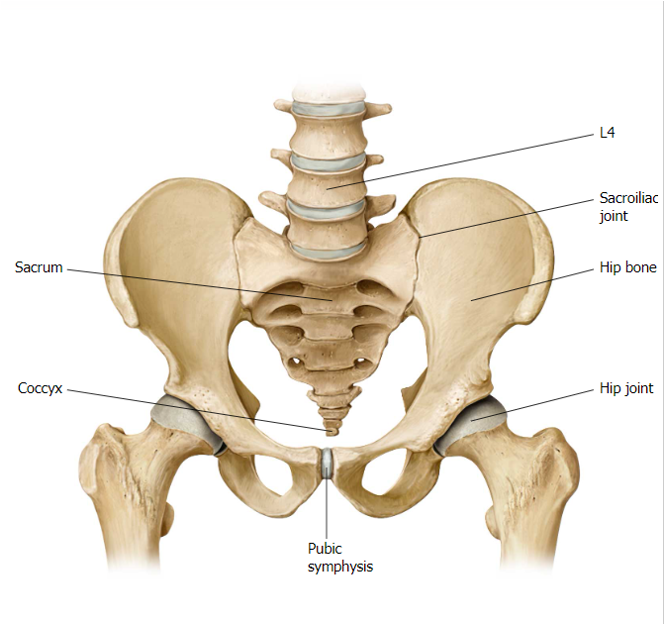

Body Weight Transfer

Vertebral Column

Sacro-Iliac Joints

Pelvic Girdle

Hip Joints

Femurs